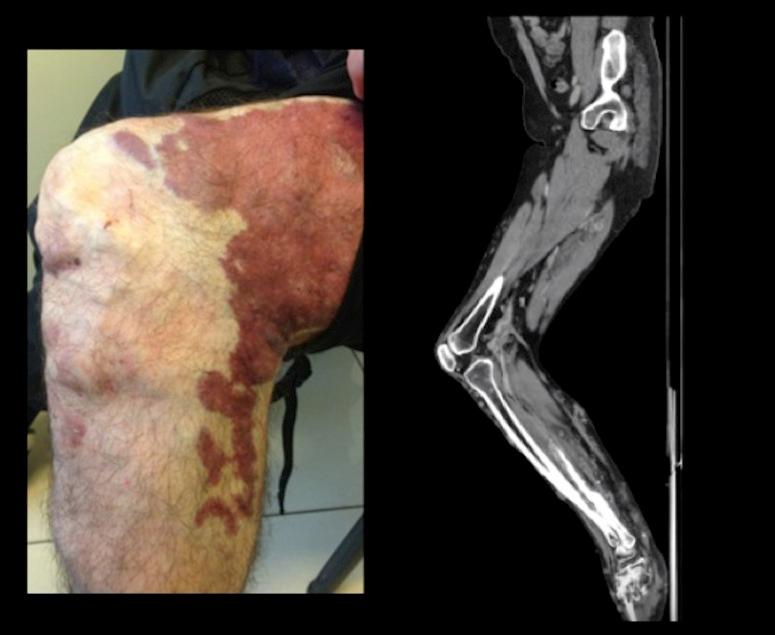

Klippel-Trenaunay syndrome (KTS) is a rare vascular malformation characterized by capillary malformation, venous malformations, and soft tissue or bone hypertrophy that affect the extremities in most cases. Knee or hip arthropathy are common associated conditions and cause serious disability. We present the case of a patient with a diagnosis of KTS and severe knee arthropathy. A 34-year-old man with KTS was referred to our hospital with severe knee arthropathy, with the joint fixed in a 90° position. CT Angiography and MRI of the left leg showed important varicose development of the superficial venous system with intraarticular vessels. After discussion of the case by a multidisciplinary committee, the patient was enrolled on a physiotherapy program and had achieved significant improvements in movement and quality of life at 12-month follow-up. Treatment of KTS is primarily conservative and a multidisciplinary approach is necessary.

克-特综合征(KTS)是一种罕见的血管畸形,其特征为毛细血管畸形、静脉畸形以及软组织或骨肥大,多数情况下累及四肢。膝关节或髋关节病是常见的相关病症,可导致严重残疾。我们报告一例诊断为KTS并伴有严重膝关节病的患者。一名34岁的克-特综合征男性患者因严重膝关节病被转诊至我院,关节固定于90°位。左腿的CT血管造影和MRI显示浅静脉系统有明显的静脉曲张形成,且存在关节内血管。经多学科委员会讨论该病例后,患者纳入了物理治疗方案,在12个月的随访中运动和生活质量有显著改善。克-特综合征的治疗主要是保守治疗,多学科方法是必要的。